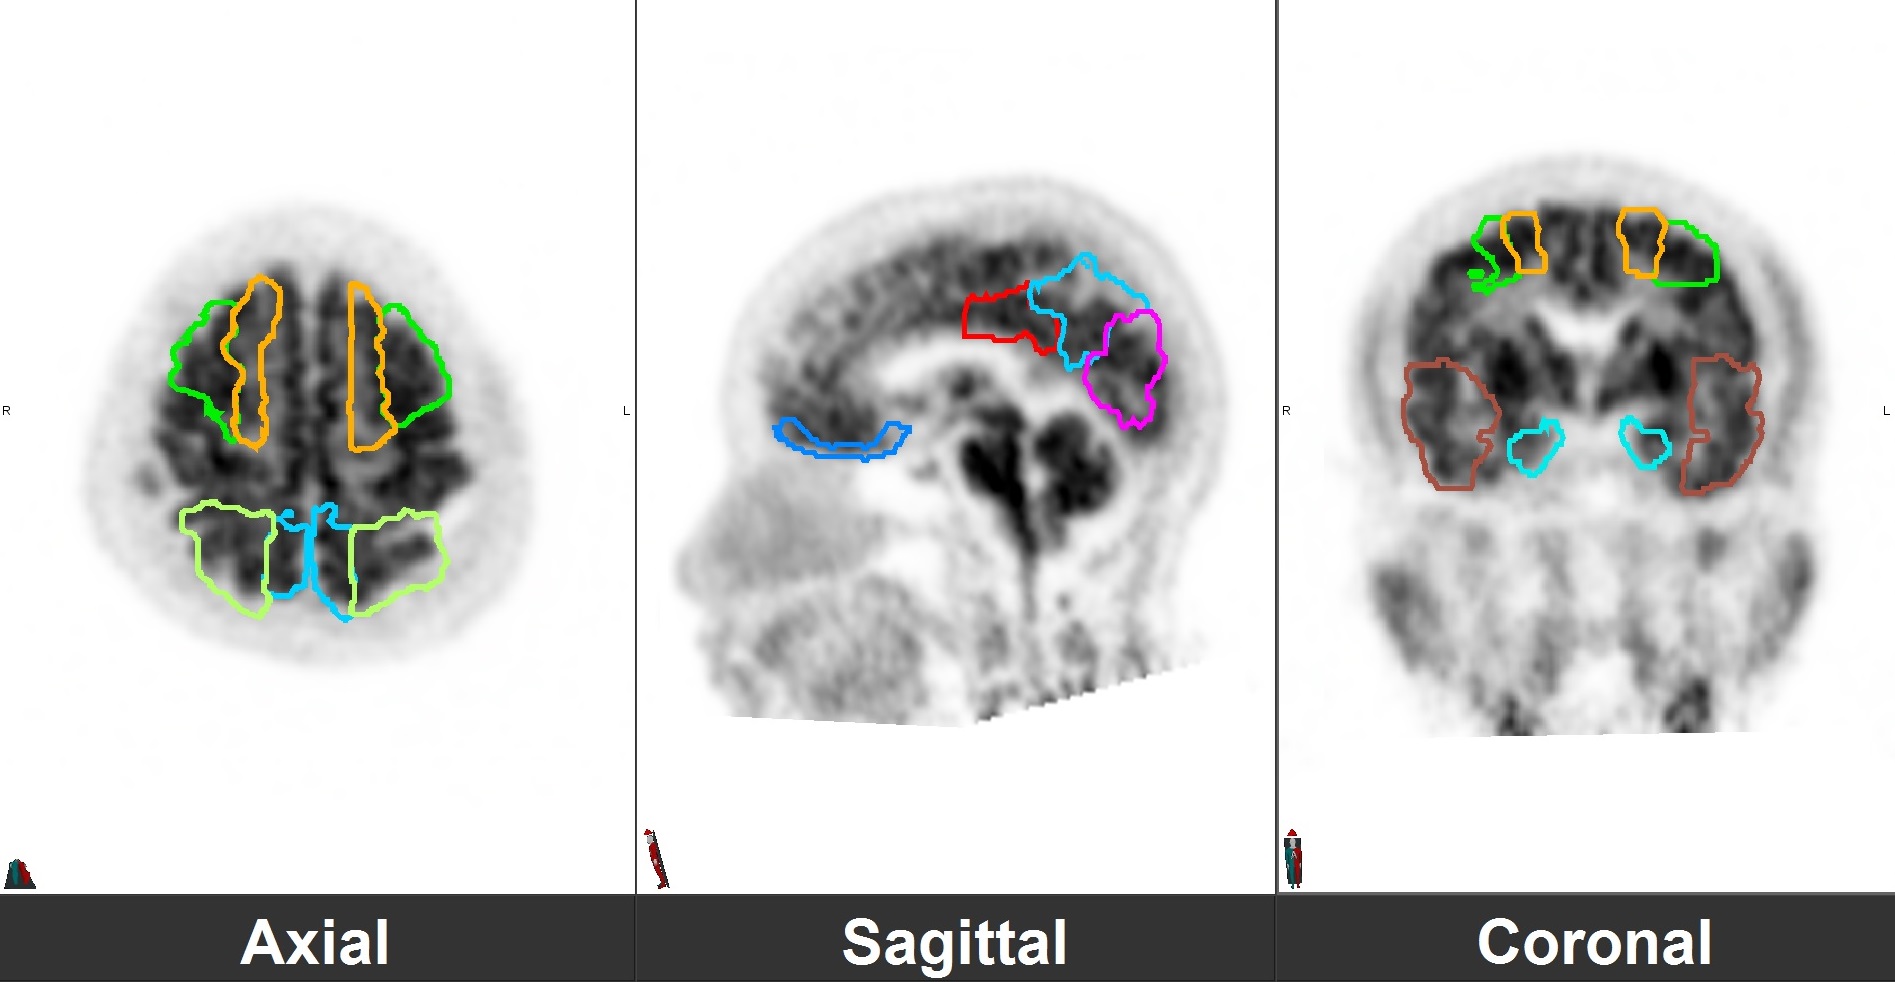

Neurological Diseases

- Dementia

PET/CT scans with special tracers can show 3-dimensional images of blood flow and biomolecules deposition in the brain for diagnosis and monitoring the therapy progress of various neurological diseases, such as Alzheimer's, Dementia, Parkinson's disease, Huntingdon's chorea and autism. In 2018, the National Institute on Aging-Alzheimer's Association (NIA-AA) had revised the definition of Alzheimer's Disease (AD) from a syndrome diagnosed by a set of clinical criteria to a biological construct using abnormal protein deposits to define AD as a unique neurodegenerative disease that can lead to dementia. Our hospital has almost 20 years of experience in producing specific tracer to detect abnormal protein deposition in the brain.

- Epilepsy

For some types of epilepsy patients, PET/CT scans can localize the epilepsy-causing focus in the brain. Modern stereotaxic neurosurgery can then cure epilepsy permanently by excising the focus.